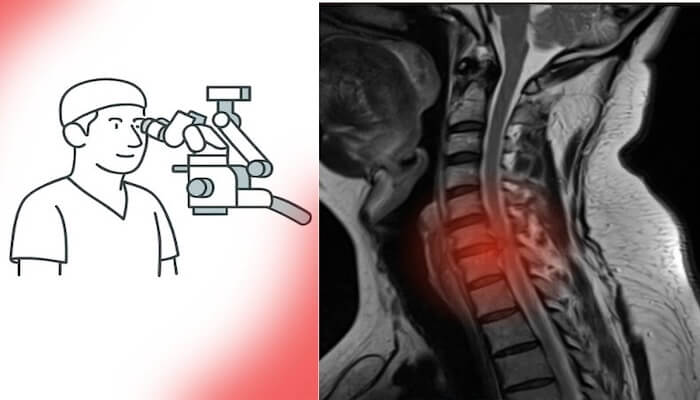

Günümüzde MR ve BT gibi ileri radyolojik görüntüleme yöntemlerine erişim son derece kolaylaştı. Artık neredeyse her şehirde donanımlı hastaneler ve modern tanı merkezleri bulunuyor. Bu sayede en küçük lezyonlar bile erken dönemde saptanabiliyor.

Türkiye’de sağlık hizmetlerine erişim ve radyolojik altyapı son yıllarda ciddi bir ivme kazandı; adeta sağlıkta zirveye ulaşıldı.Bu gelişmeler, tanı sürecini hızlandırarak hem beyin tümörü ameliyatı hem de omurga cerrahisi gerektiren hastaların erken dönemde tespit edilmesini sağladı. Eskiden geç tanı alan birçok vaka, artık uygun zamanda cerrahi müdahaleye yönlendiriliyor. Böylece erken tanı, hem nörolojik kayıpların önlenmesine hem de cerrahi başarı oranlarının artmasına katkı sunuyor.